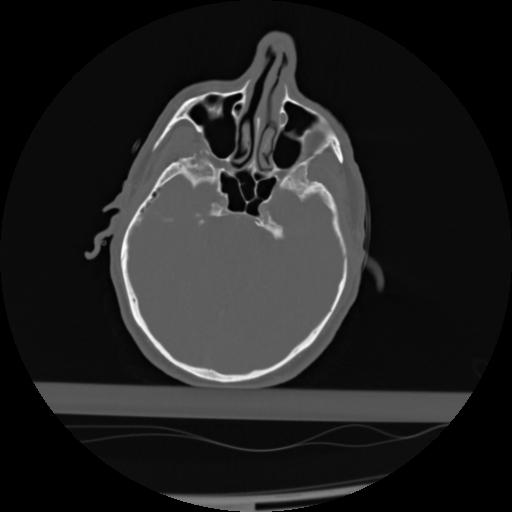

21 ANGIO,CE,Axial,3.0,ANGIO,,